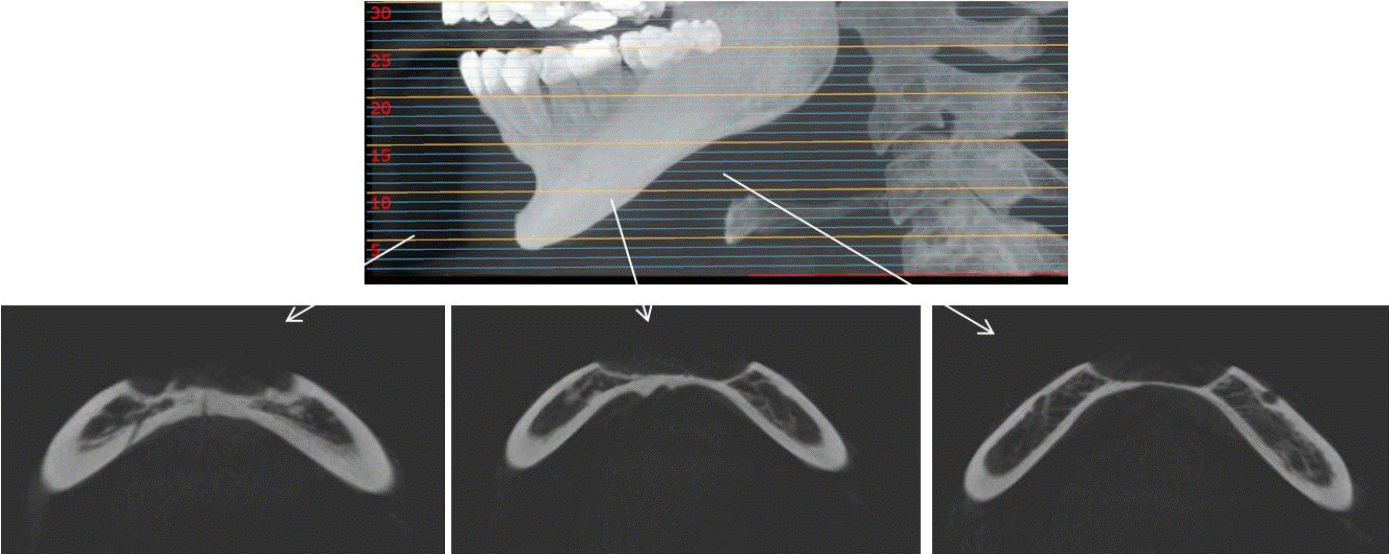

Figure 3.

Cone-beam computed tomographic axial view shows a well-circumscribed peripheral depression with smooth borders and a corticated margin.

Figure 4.

Cone-beam computed tomographic cross-sectional view of the mandible clearly demonstrates a peripheral bone depression extending from the labial to the lingual cortical plate.

32세 여성 환자의 파노라마방사선영상에서 하악 전치부 낭이 관찰되어, 정확한 진단을 위하여 본원에 의뢰되었다. 특별한 임상증상은 없었다. 파노라마방사선영상에서 하악 우측 제1소구치에서 좌측 제1소구치 치근하방에 경계가 명확하고 피질골성 변연을 가진 타원형의 방사선투과상이 관찰되었다(Fig. 1). 방사선투과상은 해당치아들과는 무관하여 치근단낭이 배제되었고, 단순골낭의 가능성을 염두에 두고 콘빔CT 검사를 시행하였다. 콘빔CT에서 중심성 골내 병소가 아닌 악골의 순측에서 설측으로 함몰된 변연성 병소가 관찰되었다(Fig. 2). 병소의 경계는 매우 평활하였고, 단면상에서는 넓은 접시모양처럼(Fig. 3), 악골 절단면상에서는 반달모양처럼 함몰되어 있었다(Fig. 4). 설측 피질골은 비박되어 있었으나 천공은 관찰되지 않았다. 함몰된 부위는 공기가 아닌 연조직의 방사선투과상으로 채워졌으나, 콘빔CT에서는 대조도가 낮아서 연조직간의 감별이 가능하지 않았다(Fig. 5). 관찰된 턱 끝 부위의 골 함몰이 해부학적 변이인지 아닌지를 감별하기 위하여 환자의 과거 병력을 알아보았다. 환자는 2년 전에 턱 끝 부위에 미용 필러 시술을 받았다고 하였다. 방사선영상소견과 문진결과를 토대로, 미용 필러와 관련된 골흡수를 의심하였다. 이후 외과적으로 미용 필러 제거와 함몰된 부위에 골이식이 시행되었다. 수술 중에 육안으로 남아있는 미용 필러와 작은 석회화 물질들이 확인되었다. 수술 후 생검에서 다핵거대세포와 결절석회화가 관찰되었고, 피부석회화(calcinosis cutis)가 의심된다는 결과를 받았다. 이상의 술 전 검사 및 술 후 소견을 종합하여, 파노라마방사선영상에서 관찰된 방사선투과상은 치성낭이나 해부학적 변이가 아니고 미용 필러에 의한 하악골 순측 골흡수로 최종 진단되었다.